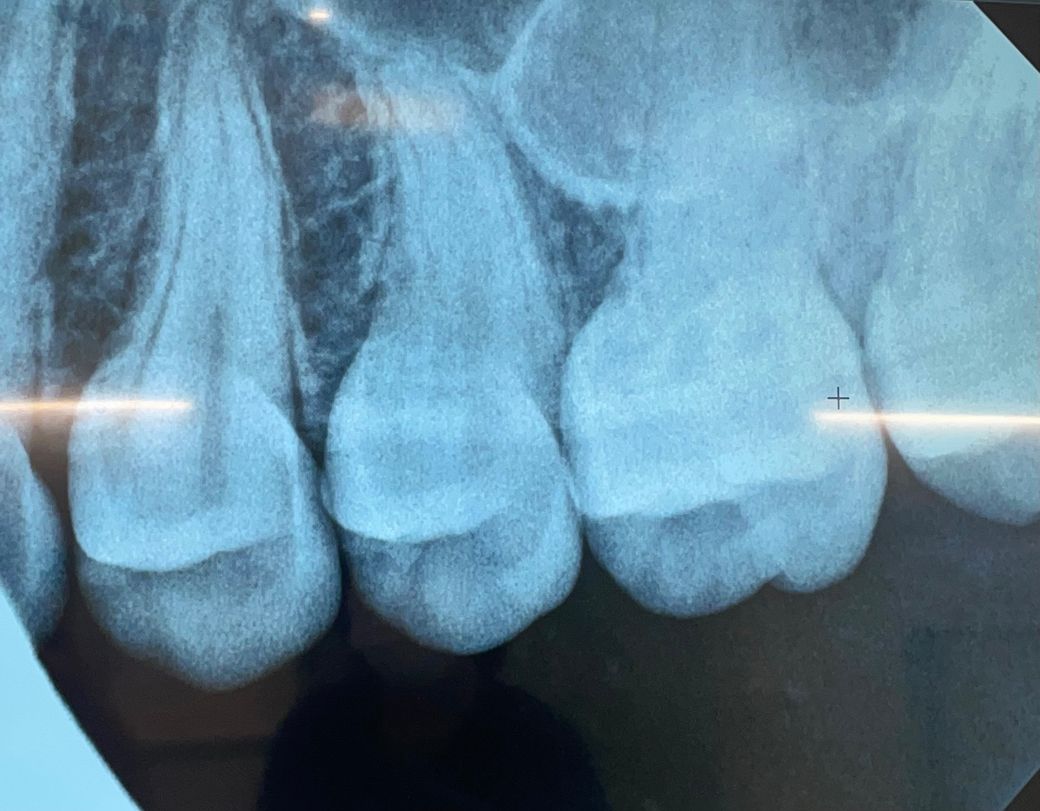

치아 사이 충치 맞는지 확인해주세요..

치아사이 충치 맞나요?

인레이+레진 치료 필요하다던데

적당한 치료일까요?

왼쪽에서 첫번째 두번째 사이에 충치가 발생해서 치료 필요하다 하셨는데 그럼 나머지 치아사이에는 충치 없는 거 맞나요?

치아 사이의 충치가 다른 치아에도 있지만 해당 부위의 충치가 더 커 보이며 사진만으로는 판별이 어렵습니다.

방사선 사진으로 봤을 경우 약간의 음영이 보이긴 합니다. 하지만 충치라고 단언할 순 없으며 육안으로 추가적인 확인이 필요할 것으로 생각됩니다.

자세한 확인을 위해서 치과에서 진료를 받아보는 것을 권유드립니다.

엑스레이 상으로 치아 사이에 충치가 잇는것처럼 보입니다. 인레이 또는 레진을 하시면될것같습니다.